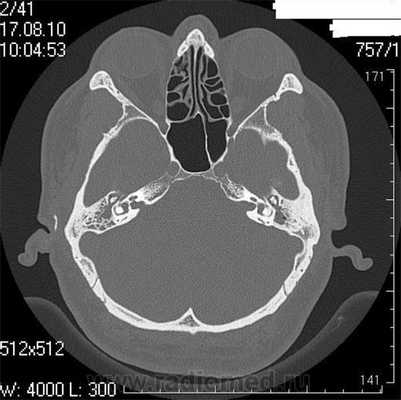

Снимок (томограмма) височных костей в осевой проекции

Во время КТ получают послойные снимки височной кости и окружающих тканей в трех плоскостях. Толщина среза составляет всего несколько миллиметров, что позволяет врачу-рентгенологу рассмотреть не только все анатомические образования, но и минимальные патологические изменения.

На полученных снимках хорошо видны следующие структуры:

На КТ-снимке виден перелом пирамиды височной кости (указан стрелками)